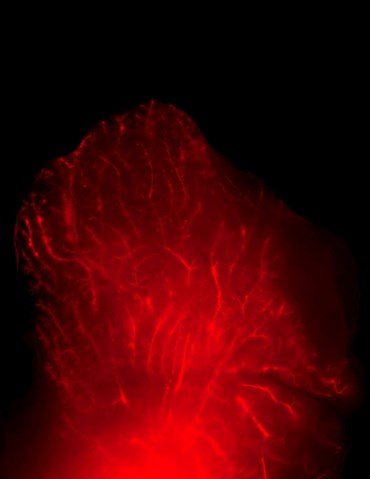

Para perceber se a terapia atingia outros tecidos, o que poderia comprometer um tratamento em humanos, a equipa utilizou um marcador fluorescente ligado ao ARN de interferência para observar, por microscopia, o seu comportamento. “Não vimos quaisquer sinais do ARN de interferência em tecidos periféricos, indicando que as moléculas são apanhadas pelas glândulas mamárias e não entram na corrente sanguínea”, explicou ao PÚBLICO Amy Brock, uma das autoras do estudo que agora trabalha na Universidade de Austin, no Texas.